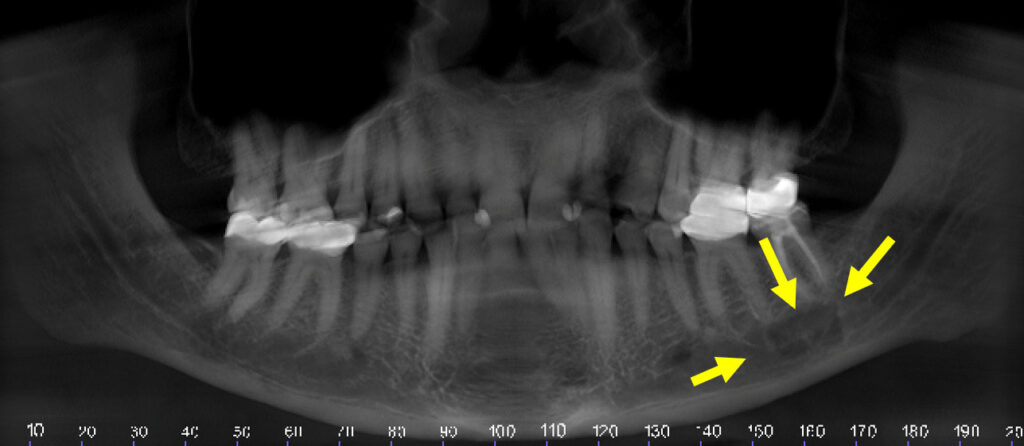

40-year-old woman with lesion

A 40-year-old woman presented with a lesion located at the periapical area of tooth #30.

19-year-old woman undergoing a recall exam

An asymptomatic 19-year-old woman undergoing a recall exam.